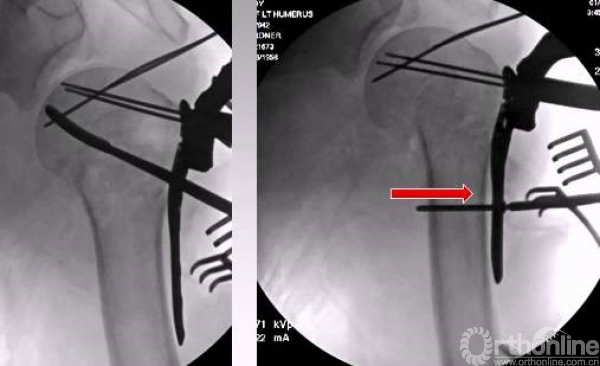

在此病例中,为了复位良好,舍弃了肱骨近端与钢板贴服。

以钢板进行复位,然后用皮质骨螺钉进行提拉 完成肱骨近端解剖形态。